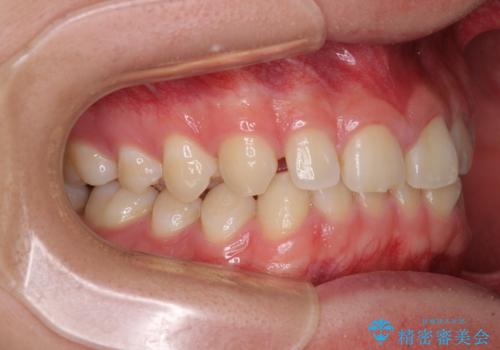

隙間とデコボコを治したい ワイヤー装置による矯正治療

舌の突出癖がなかなか改善されず、治療開始時よりも隙間が大きく開いてしまう時期がありましたが、最終的にしっかりと閉じて終了することができました。